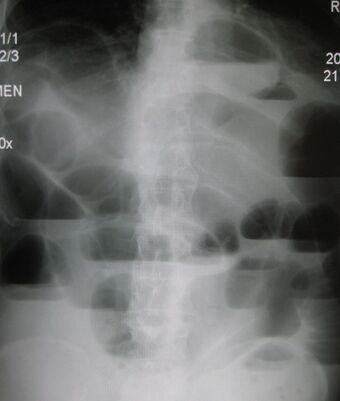

| Upright abdominal X-ray demonstrating a small bowel obstruction. Note multiple air fluid levels. | |

Radiological signs of bowel obstruction include bowel distension and the presence of multiple (more than six) gas-fluid levels on supine and erect abdominal radiographs. Ultrasounds may be as useful as CT scanning to make the diagnosis.[17]

Contrast enema or small bowel series or CT scan can be used to define the level of obstruction, whether the obstruction is partial or complete, and to help define the cause of the obstruction. The appearance of water-soluble contrast in the cecum on an abdominal radiograph within 24 hours of it being given by mouth predicts resolution of an adhesive small bowel obstruction with sensitivity of 97% and specificity of 96%.[18]